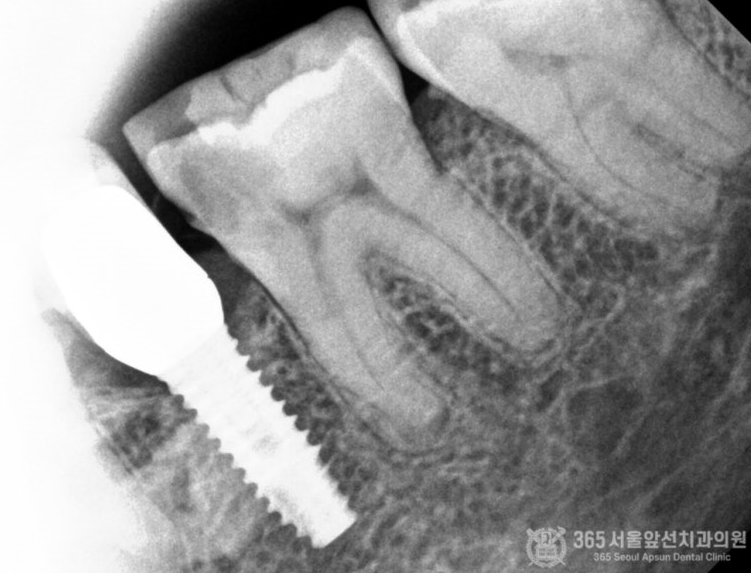

촬영일시 : 2024.06.01 엑스레이 사진에서도 임플란트 옆 치아에 심한 치아우식증이 관찰됩니다. 치아우식증이 신경까지 진행되었기 때문에 이 경우에는 신경치료가 필요하겠습니다.